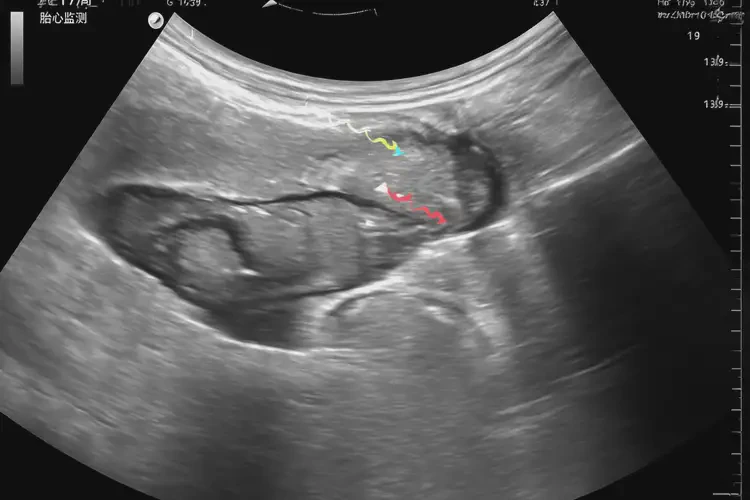

孕17周4天胎心139正常嗎(圖1)

孕17周4天胎心139正常嗎(圖2)

孕17周4天胎心139正常嗎(圖3)

孕17周4天胎心139正常嗎(圖4)